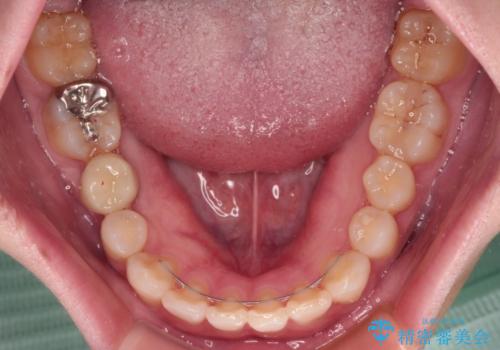

- 咬み合わせと前歯のデコボコを気にして来院された患者様です。

前から5番目の永久歯が3本欠損しており、乳歯が残存している状態でしたが、インビザラインでも十分に対応可能と判断し、インビザラインにて矯正治療を行うこととしました。

右下の残存している乳歯は萌出しきれておらず、全く咬み合っていない状態であり、インビザラインにて移動できない可能性があるため、ワイヤー矯正の併用も念頭に置いて治療を開始しました。

今回は部分的にワイヤー矯正を用いましたが、右下の乳歯は全く動かなかったため、抜歯をした上でインプラントを埋入し、オールセラミッククラウンにて補綴治療を行いました。